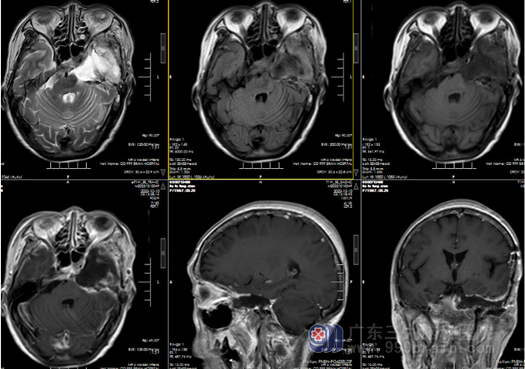

手术耐受情况良好,术后一般情况恢复良好。左侧眼睑下垂,左侧面瘫,左耳听力基本丧失等情况同前 ;神经影像学显示肿瘤大部切除 ;术后治疗 10 天,拆线出院。1月后放疗 45Gy/15f。

图 5 经颞下入路左侧蝶岩斜区脑膜瘤切除术后复查:左侧额颞顶部呈术后改变,术区顿骨内板下示弧形各序列高低混杂信号影,相应术区皮下软组织肿胀伴一引流管留置;右侧额颢顶部、左侧额部硬膜下示弧形长T2信号局部间杂积气影。原左侧鞍区、海绵窦、岩斜区病变大部分切除术后,术区及术道示条片状各序列高低混杂信号影,增强后术区周缘及邻近脑膜可见强化,残留病变仍可见明显强化,邻近脑膜强化。